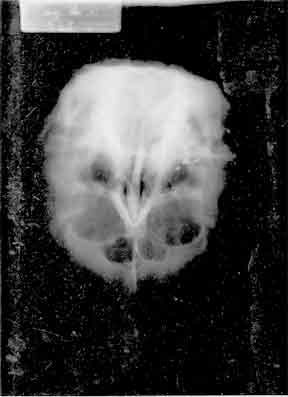

| False photograph received from the office of Dr. Harold J. Hoffman, Toronto Hospital for Sick Children | ||||||||||||

| 43 Metallic "Surgical Clips"? Or CIA brain electrode implant research? No consent for this intrusion! | ||||||||||||